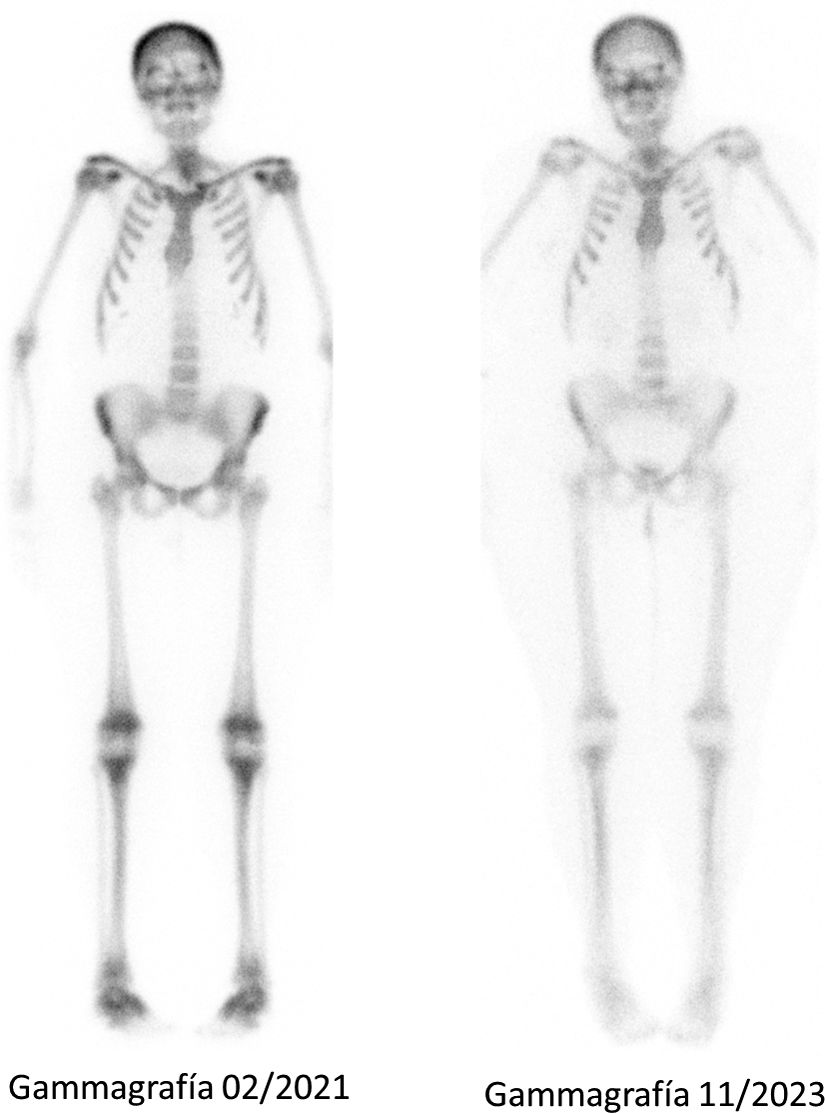

En marzo de 2021 es valorada en reumatología por poliartralgias difusas y dolor en columna lumbar de 2 meses de evolución. Entre los parámetros analíticos destacaba calcio corregido 9,5mg/dl, albúmina 4,1g/dl, magnesio 1,6mg/dl, fosfato 4,4mg/dl, fosfatasa alcalina 149U/l, 25-OH vitamina D 39,9ng/ml, PTH<6pg/ml, calciuria 584mg/24h, fosfaturia 1.035mg/24h, factor reumatoide y anticuerpos antipéptido citrulinado negativos, proteína C reactiva 1mg/l, VSG 10mm/h. En el estudio radiográfico se observó aumento de densidad ósea y zonas líticas en columna lumbar, hombros, caderas y rodillas, todas ellas sugestivas de hiperparatiroidismo. En la gammagrafía ósea (99mTc-difosfonatos) se objetiva patrón de «superscan» metabólico, con mayor grado de actividad en calota, pelvis y miembros inferiores (fig. 1).

Figura 1.

Gammagrafía ósea (99mTc-difosfonatos). Patrón de «superscan» metabólico, con mayor grado de actividad en calota, pelvis y miembros inferiores (izquierda). Disminución de las zonas de captación tras 2 años de suspensión de teriparatida y reconversión de bypass gastroileal (derecha).

En septiembre de 2021 se realiza reversión de bypass gástrico y se suspende teriparatida. A partir de entonces, se objetiva una mejoría progresiva de la clínica articular/axial, disminución de las áreas de captación en el estudio gammagráfico (fig. 1) y estabilidad en los niveles de calcemia 11,4mg/dl y calciuria 182mg/24h. La paciente no ha presentado nuevos episodios de tetania.

Después de casi 4 años de administración de teriparatida la paciente desarrolló manifestaciones clínicas y radiográficas de hiperparatiroidismo, a pesar de la falta de control óptimo de sus niveles de calcio sérico. En ese sentido, la gammagrafía ósea tiene un valor y no es útil para su diagnóstico, pero sí para valorar la extensión de la afectación esquelética13. La intensidad de la hipercaptación del trazador en el hiperparatiroidismo (primario) parece correlacionarse con la gravedad de las alteraciones radiográficas11.

Hasta ahora no hay casos descritos de pacientes con uso crónico de teriparatida con síntomas articulares, patrón radiográfico sugestivo de hiperparatiroidismo inducido (vértebras en jersey de rugby) y patrón gammagráfico de «superscan», con mejoría progresiva tras reversión de bypass gastroileal.